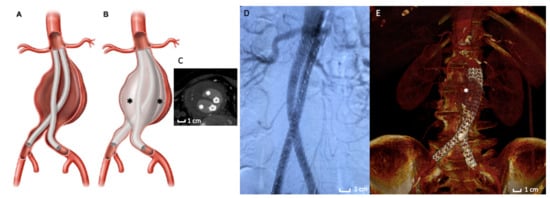

A few years later, an evolution of the Enovus was proposed for human application with the name of Ovation Endograft (Endologix, Irvine, CA, USA). After successful animal investigations [72], the platform was tested in clinical trials with positive feedback, which was a fundamental evolution in the use of polymers in the EVAR field. The endograft is based on a new concept design separating fixation from sealing—fixation activity is assured by a suprarenal stent and anchors (not different from traditional suprarenal EVAR devices), while sealing activity is based on inflatable O-rings filled with a low-viscosity, non-embolic, radiopaque fill polymer instead of traditional self-expanding stent grafts. The adaptability of the proximal O-ring filled with polymer to the patients’ aortic neck anatomy determines a substantial increase in EVAR feasibility [73,74]. In other words, polymer injected in the O-rings creates a customized circumferential sealing at the proximal aneurysmal neck level, without executing any outward pressure on the aortic neck wall once the final deployment is completed. This assumption comes with a benefit in reducing aortic neck dilatation and consecutive endograft migration, a typical complication of SESGs. All these features define the revolutionary concept of “Custom Seal” as a tailored adaptation of polymer rings to the aortic wall, including wall calcification, wall thrombosis, and aortic tortuosity [75,76,77].

The importance of polymer in the proximal endograft zone is even greater in the exploratory experience of the use of the Ovation endograft in the treatment of patients with Juxtarenal-AAA (those aneurysms involving the infrarenal abdominal aorta adjacent to or including the lower margin of renal artery origins [87]) and is unfit for traditional open surgery repair of Fenestrated-EVAR. In these particular cases, the endograft is deployed, letting the sealing ring land very close to the lowermost renal artery (Figure 3A,E,F) [88,89]. The correct deployment assures the stability of this implant of the endograft and, in particular, by the sealing activity of polymer rings, including the O-ring capability to adapt to irregular anatomies.

Figure 3. Ovation stent graft. (A) Picture of the Ovation endograft. Proximal sealing is assured by polymer filled O-rings (red circle) adapted to the aortic neck anatomy. (B,C) Details of the axial appearance of O-rings well-opposed to the aortic wall. (D) Intraoperative image of the Ovation stent graft deployed. The asterisk (*) highlights the polymer filled O-rings. (E) Angiographic acquisition that reveals the good exclusion of the AAA by the polymer filled O-rings (*). (F) 3D volume rendering of Computed Tomography Angiography at 3-months follow-up that shows the correct exclusion of the AAA. The asterisk (*) indicates the polymer filled O-rings located in the proximal fixation zone.